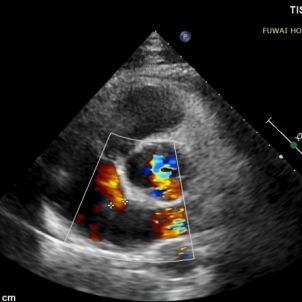

Angesichts der Nähe des Defekts zur Koronar arterie stellte ein herkömmlicher Metall okluder ein Kompression risiko dar, insbesondere bei körperlicher Anstrengung. Ein biologisch abbaubarer ASD-Okk luder (BDASD-I. 18mm) wurde daher aufgrund seiner Flexibilität, seines geringeren Risikos einer langfristigen mechanischen Verletzung und seiner Fähigkeit, sich nach Abschluss der Verschluss funktion in Kohlendioxid und Wasser abzubauen, ausgewählt.

1-day postoperative TTE revealed that the occluder is in good shape without residual shunt (see last figure).